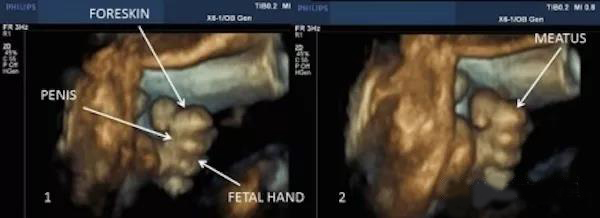

曾经有新闻报道,台湾一名孕妈在超声波产检时,看到了27周的男胎儿居然正在*慰自**,小JJ还会勃起,这位准妈妈看了又好笑又害臊。妇产科医生说,胎儿*慰自**是正常现象,只是很难被捕捉到罢了。

《美国妇产杂志》也曾记载了一位女性胎儿*慰自**的全过程,研究者看到一个32周的女宝宝用右手手指触摸阴蒂的过程。因为宝宝在妈妈肚子里4个月的时候生殖系统就已经发育成型了!